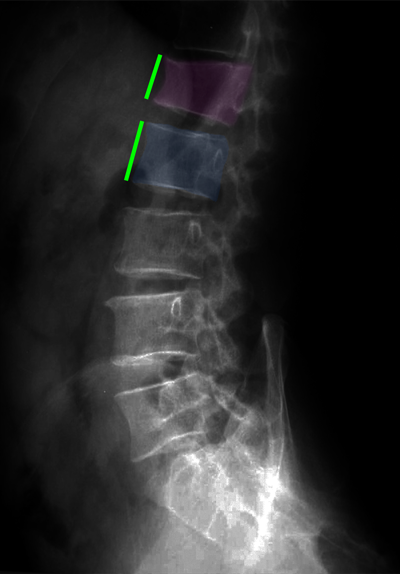

Κάταγμα 01 (φούξια) με μείωση του ύψους του σπονδύλου σε σύγκριση με τον υποκείμενο υγιή σπόνδυλο (μπλέ)(αριστερά). Κυφοπλαστική με ανάταξη του κατάγματος και επαναφορά του ύψους του σπονδύλου στο φυσιολογικό (δεξιά).